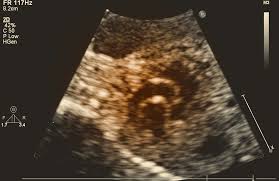

The exam uses sound waves that "echo" off of the structures of the fetus’ heart. A machine analyzes these sound waves and creates a picture, or echocardiogram, of their heart’s interior. This image provides information on how your baby’s heart has formed and whether it’s working properly.

It also allows your doctor to see the blood flow through their heart. This in-depth look allows your doctor to find any defects or abnormalities in the baby’s blood flow or heartbeat.